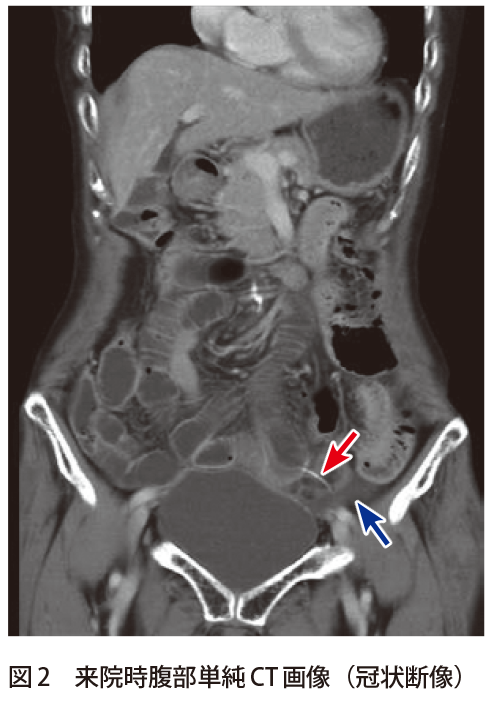

解答 解説 激しい腹痛で救急搬送された70歳代女性 実践 画像診断q A 羊土社 レジデントノート 羊土社